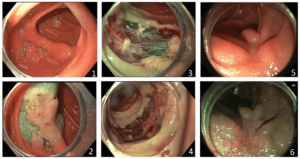

Een 57-jarige vrouw met een blanco voorgeschiedenis werd verwezen in verband met pijn in epigastrio en pyrosisklachten zonder dat er sprake was van passageklachten of gewichtsverlies. Bij gastroscopie werd in het pars descendens/pars horizontalis van het duodenum, op ruime afstand van de papilla major, een sessiele adenomateus-ogende laesie gezien. De laesie lag over een plooi gedrapeerd en besloeg de helft van circumferentie, waarbij de geschatte grootte circa 4 bij 3 centimeter was (figuur 1). De biopten toonden een tubulovilleus adenoom met laaggradige dysplasie. De klachten die aanleiding gaven tot het verrichten van de gastroscopie konden echter niet verklaard worden door het duodenumadenoom.

Er werd een coloscopie verricht ter uitsluiting van advanced neoplasie, deze toonde geen afwijkingen. Een piecemeal poliepectomie van dit sporadisch duodenumadenoom werd ingepland waarbij tevoren de risico’s werden besproken. Gezien het voornemen de laesie middels koude lis piecemeal resectie te verwijderen wordt dit risico veel lager ingeschat dan bij conventionele EMR. Tijdens de endoscopie werd de laesie opgespoten met gelofusine- en indigokarmijnoplossing en vervolgens in piecemeal met een dedicated koude poliepectomiesnaar macroscopisch radicaal verwijderd (figuur 2, 3 en 4). De procedure verliep ongecompliceerd. Postprocedureel werd voor 3 weken protonpompremming voorgeschreven. Een half jaar later werd er een gastroscopie verricht ter controle. Hierbij werd een fraai litteken gezien zonder aanwijzingen voor recidief of restant poliepweefsel (figuur 5 en 6). Surveillancerichtlijnen voor endoscopisch verwijderde sporadische duodenumadenomen zijn niet beschikbaar, met patiënt werd gastroscopiesurveillance over 3 jaar afgesproken. Concluderend was er bij deze patiënte sprake van een sporadisch duodenumadenoom, succesvol verwijderd middels piecemeal koude snaar poliepectomie.